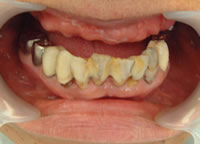

症例1 2007 9/14 更新

治療前 治療完了

治療前

平成16年7月7日

治療完了

平成19年5月1日

(治療期間:2年10ヶ月)